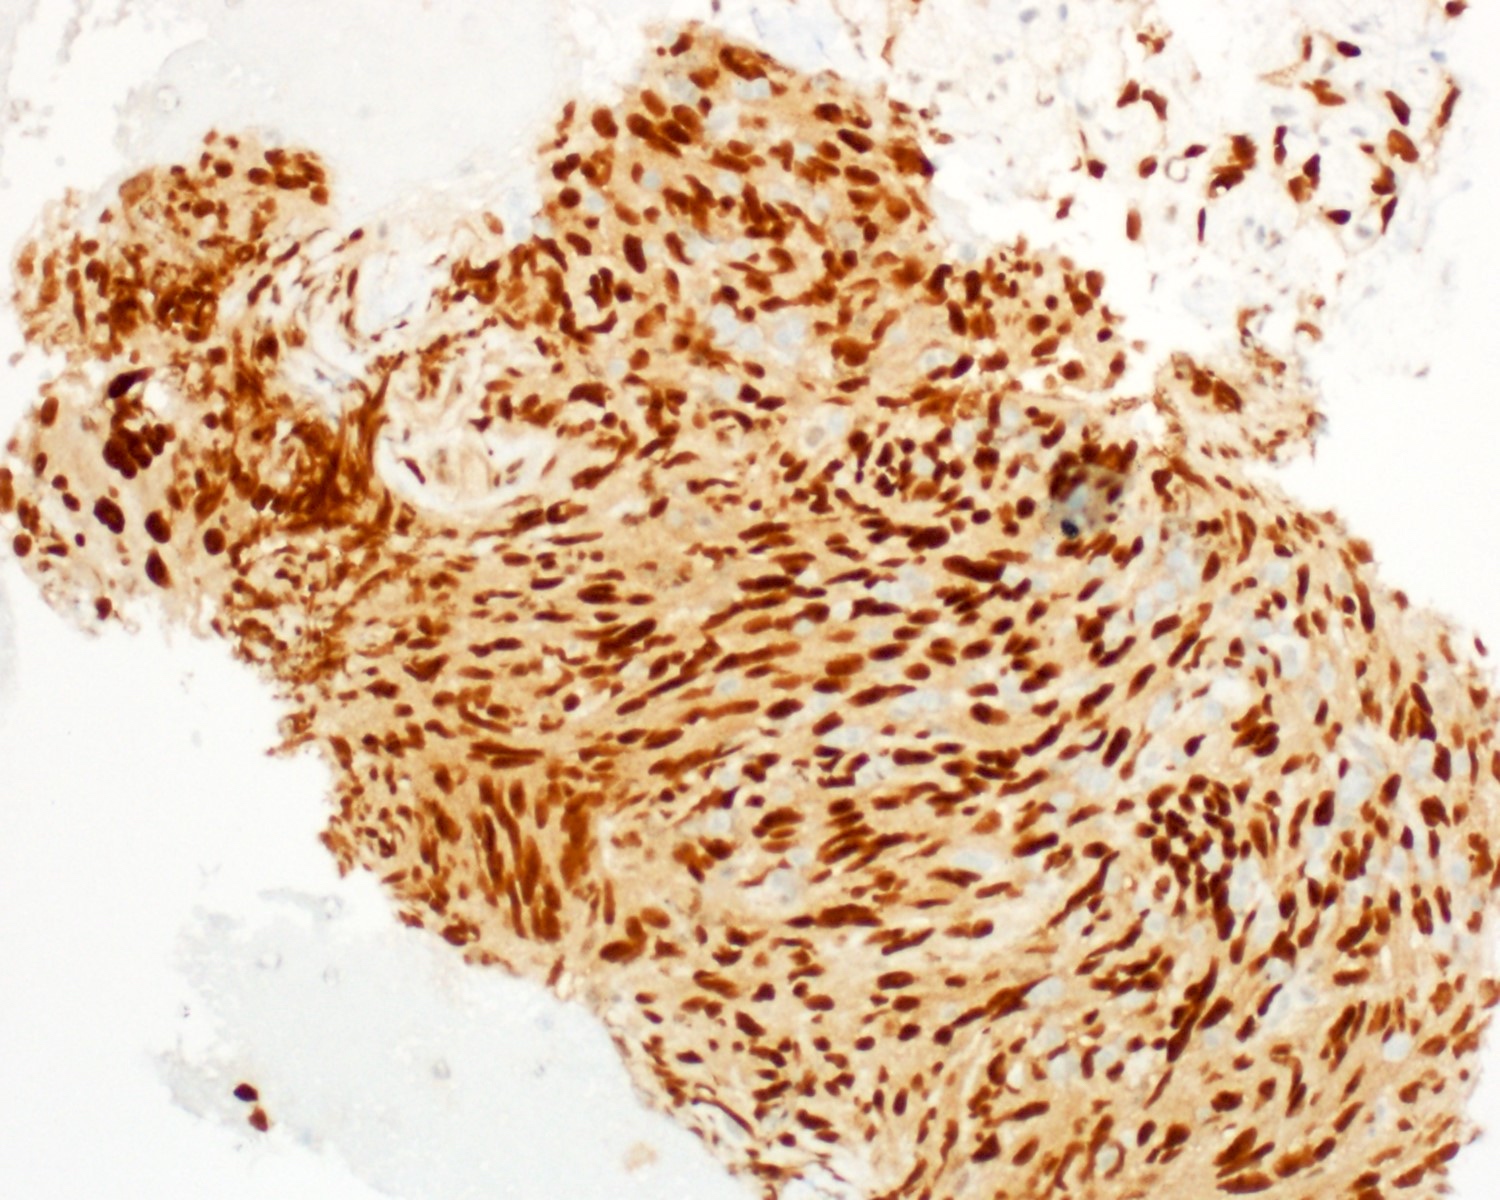

Positive stains

- ERG (nuclear)

- CD31 (membranous)

- CD34 (variable ~50%)

- Factor VIII

- VEGF (Sci Rep 2021;11:9362)

- FLI1

- Ulex europaeus agglutinin I (UEA1) (Histopathology 1986;10:1153)

- D2-40 (podoplanin)

A 55 year old man presents with abdominal pain, weight loss and hepatomegaly. Laboratory studies reveal elevated liver enzymes but normal alpha fetoprotein levels. A liver core needle biopsy is performed. ERG immunohistochemistry is shown in the second image above. What is the most likely diagnosis?

E. Liver angiosarcoma. The histopathology shows nests and sheets of highly atypical neoplastic cells with hyperchromatic and pleomorphic nuclei, which are highlighted by ERG immunohistochemistry in the second image above. This makes liver angiosarcoma the most likely diagnosis.